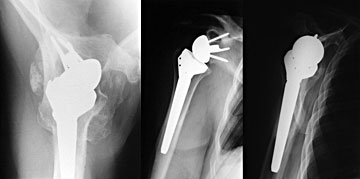

Ist der RM-Schaden weit fortgeschritten, kommt es zu knöchernen

Reaktionen am Schultergelenk, es findet sich eine sogenannte Defektarthropathie.

Hier sind die Muskeln definitiv irreversibel geschädigt und

ein Rekonstruktion der RM führt zu keiner funktionellen Verbesserung.

Meist dominieren neben dem Funktionsverlust die Schmerzen. Hier

bietet die Implantation einer inversen Schulterprothese gute Behandlungsmöglichkeiten

und führt zu einer Besserung der Funktion und deutlichen Reduktion

der Schmerzen. Durch das Vertauschen von Humeruskopf und Pfanne

entlastet man den Delta Muskel und erreicht somit eine bessere Beweglichkeit.

So lässt sich ein dauerhaftes und für den Patienten akzeptables

Ergebnis erreichen.

|

Abbildung:

Defektarthropathie |

Inverse Prothese |

Gerade die Funktion der Schulter kann durch die

Implantation einer inversen Prothese dauerhaft deutlich gebessert

werden.